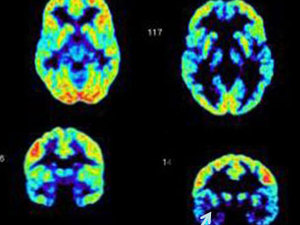

Over winter break the newlyweds drove down to New Haven for a visit and I snuck them into the lab so I could scan their brains. It was supposed to be harmless – in fact my other sister and her husband had done the same thing years ago after they got married, as an amusing way for me to tell them the differences in their personalities and warn them of the inevitable times they’d clash. It’s sort of like a Meyers-Briggs thing: I can tell you the type of personality you have from the lights in your brain – flashes of blue, red and yellow amid darker patches of black.

And that’s how, a few weeks later, I ended up reading their scans over breakfast before heading out to teach my morning class. That’s when I saw it, right in front of me: a dark patch in Sam’s orbital cortex, just behind the eyes. I recognized it immediately. The orbital cortex is the part of the brain involved with ethical behavior, moral decision-making and impulse control. It acts like a damper on the amygdala, the part of the brain associated with aggression and appetites. Every serial killer’s brain scan I’ve ever seen – and I mean every single one – has had that dark patch in the orbital cortex. The same one I saw in Sam’s brain, right behind his eyes. The one that means there’s an imbalance and the orbital cortex isn’t doing its job.

And the result of this particular work stoppage? The amygdala – the part of your brain driving your id-type behaviors – your unchecked rage, violence, eating, sex, drinking, all of it – takes over. You become a sociopath. According to my data, you’re likely to be a serial killer.

“Because,” he started, pulling the scan out of the envelope. “Remember we both got scanned last week, for the final baselines?” I nodded. “This one’s yours. Look at the orbital cortex.”

I did and immediately saw what he referenced: a dark patch, right behind my eyes. Almost identical to what I’d seen in Sam’s scan. I stared at it in silence as Travis continued. “So, based on this, I don’t think we should be so certain of our theory. I mean, we thought everyone who had this profile would end up being a killer, right? But you having it sort of refutes that whole thing, doesn’t it? You’d never kill anybody.” He laughed. I hoped I didn’t wince at the sound of it, like nails on a chalkboard. “So I figure we must be wrong. At least, we might be – the theory needs more work, anyway. That’s why I don’t think we should publish. I don’t think we can. Not in good conscience.”